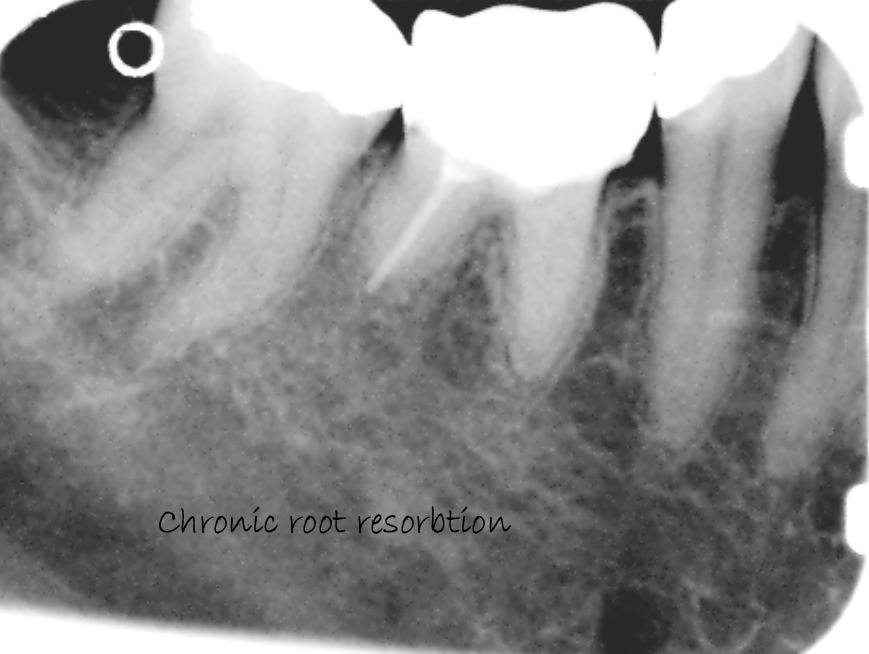

Chronic root resorbtion